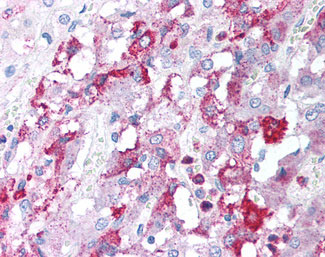

Anti-GFRA3 antibody IHC of human adrenal. |